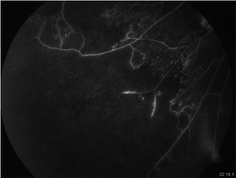

Fig. 15.4

Fluorescein angiogram of inferotemporal quadrant of an eye with retinal vasculitis showing extensive areas of capillary non-perfusion and early retinal neovascularization

Tubercular retinal vasculitis typically involves the retinal veins, i.e., it causes retinal periphlebitis. It has two distinguishing features that can help in making a clinical diagnosis in high-endemic countries: presence of healed or active choroiditis patches usually overlying blood vessels and large areas of capillary non-perfusion (on fluorescein angiography) in segments drained by the involved veins (Figs. 15.3a, b and 15.4). Common complications include macular edema, retinal neovascularization, vitreous hemorrhage, and tractional retinal detachment.

It is most useful in patients with retinal vasculitis in demonstrating areas of capillary non-perfusion and associated neovascularization (Fig. 15.4) [9]. In MSC, active margins show initial hypofluorescence and late hyperfluorescence while healed areas show transmission hyperfluorescence or blocked hypofluorescence depending on RPE atrophy or proliferation. It can also help in the diagnosis choroidal neovascular membranes that may complicate MSC.